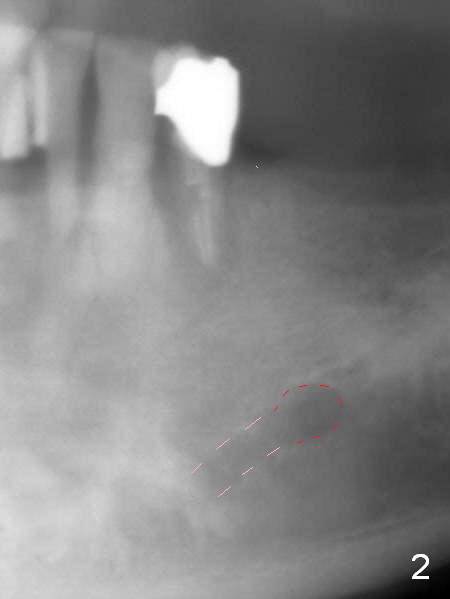

A 72-year-old man presents to clinic for implants because of pain associated with wearing the lower partial. The teeth #21, 24, 25 and 31 seem to be non-salvageable and are going to be replaced by implants so that the lower RPD can be reused (Fig.1). The edentulous ridge is atrophic (Fig.9 *). The upper complete denture appears to be functional. Since the tooth #21 is symptomatic (Fig.2) and the patient has chronic TMJ dislocation, the affected tooth is extracted first (Without antibiotic socket treatment) for immediate implant (Fig.3 (1.5 mm drill (placed more lingually)). The lower RPD is used as a surgical guide (Fig.4 (3 mm drill in place)). When a 3.8x16 mm implant is placed with bone graft (Fig.5 *), the underlying neurovascular bundle is undetected. A small field of panoramic X-ray is retaken; it seems that there is enough clearance from the Mental Foramen (Fig.2,6,7 (red dashed line)) and the Incisive Canal (pink dashed line). The implant is then placed 2 mm more apically (Fig.7) to reduce the chance of periimplantitis since the buccal plate is lost. A 5.5x5(5) mm abutment is placed (Fig.5) with more graft. The access of the abutment is left open so that a part of periodontal dressing is inserted for additional retention (Fig.8,9). The RPD is placed back for adaptation of the dressing. The patient is advised not to wear the RPD postop to reduce micromovement.